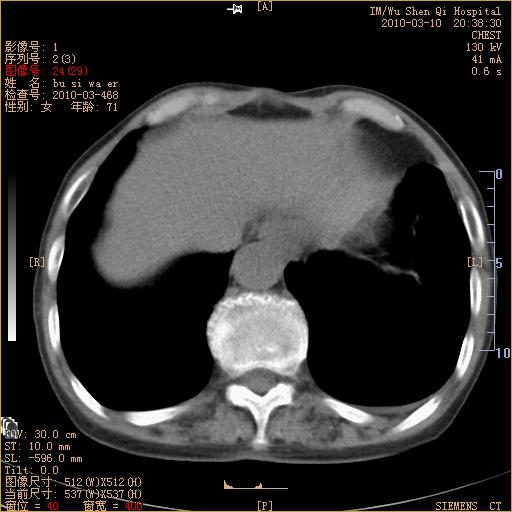

以下是引用随光逐影在2010-3-11 0:41:00的发言:[br]1)考虑左肺及右肺上叶继发性肺结核并左肺炎症感染。2)左侧支气管内膜结核可能;建议必要时行纤支镜检查。3)肺气肿。4)心包膜增厚(或少量心包积液)。5)左侧胸腔积液。